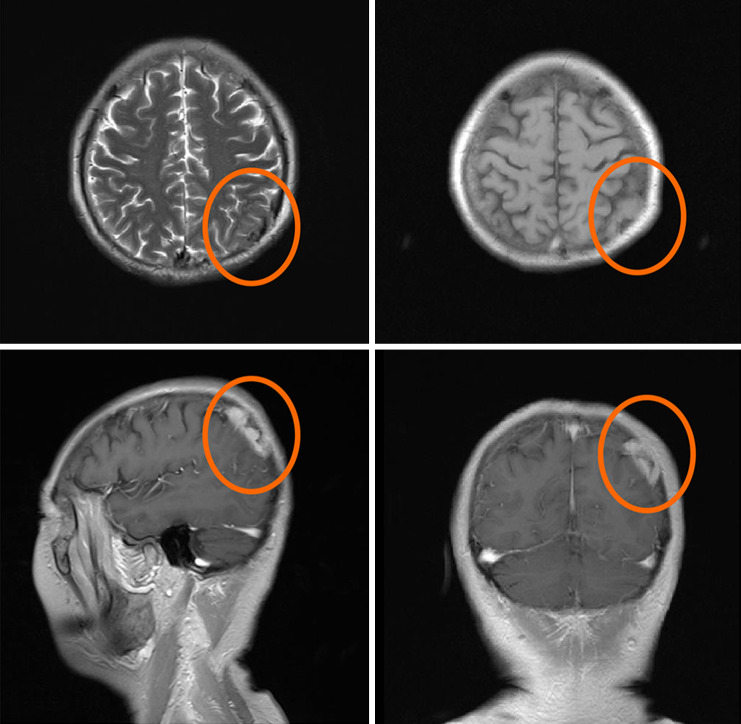

Case description: We report the case of a 65-year-old female patient with advanced lung adenocarcinoma (LUAD) who developed bone and adrenal gland metastases following treatment with gefitinib. Next-generation sequencing (NGS) of a biopsy specimen revealed the co-occurrence of MET amplification and EGFR exon 19 deletion mutation. The combined treatment of savolitinib and gefitinib effectively controlled the disease, resulting in a favorable long-term clinical outcome. With continued follow-up through April 2025, the patient has maintained progression-free survival (PFS) over 8 years. However, monitoring revealed the patient had grade 4 peripheral edema, and negative circulating tumor DNA (ctDNA), which necessitated a savolitinib dose reduction. Subsequent minimal residual disease (MRD) assessments and radiological scans revealed a remarkable therapeutic response with sustained efficacy.